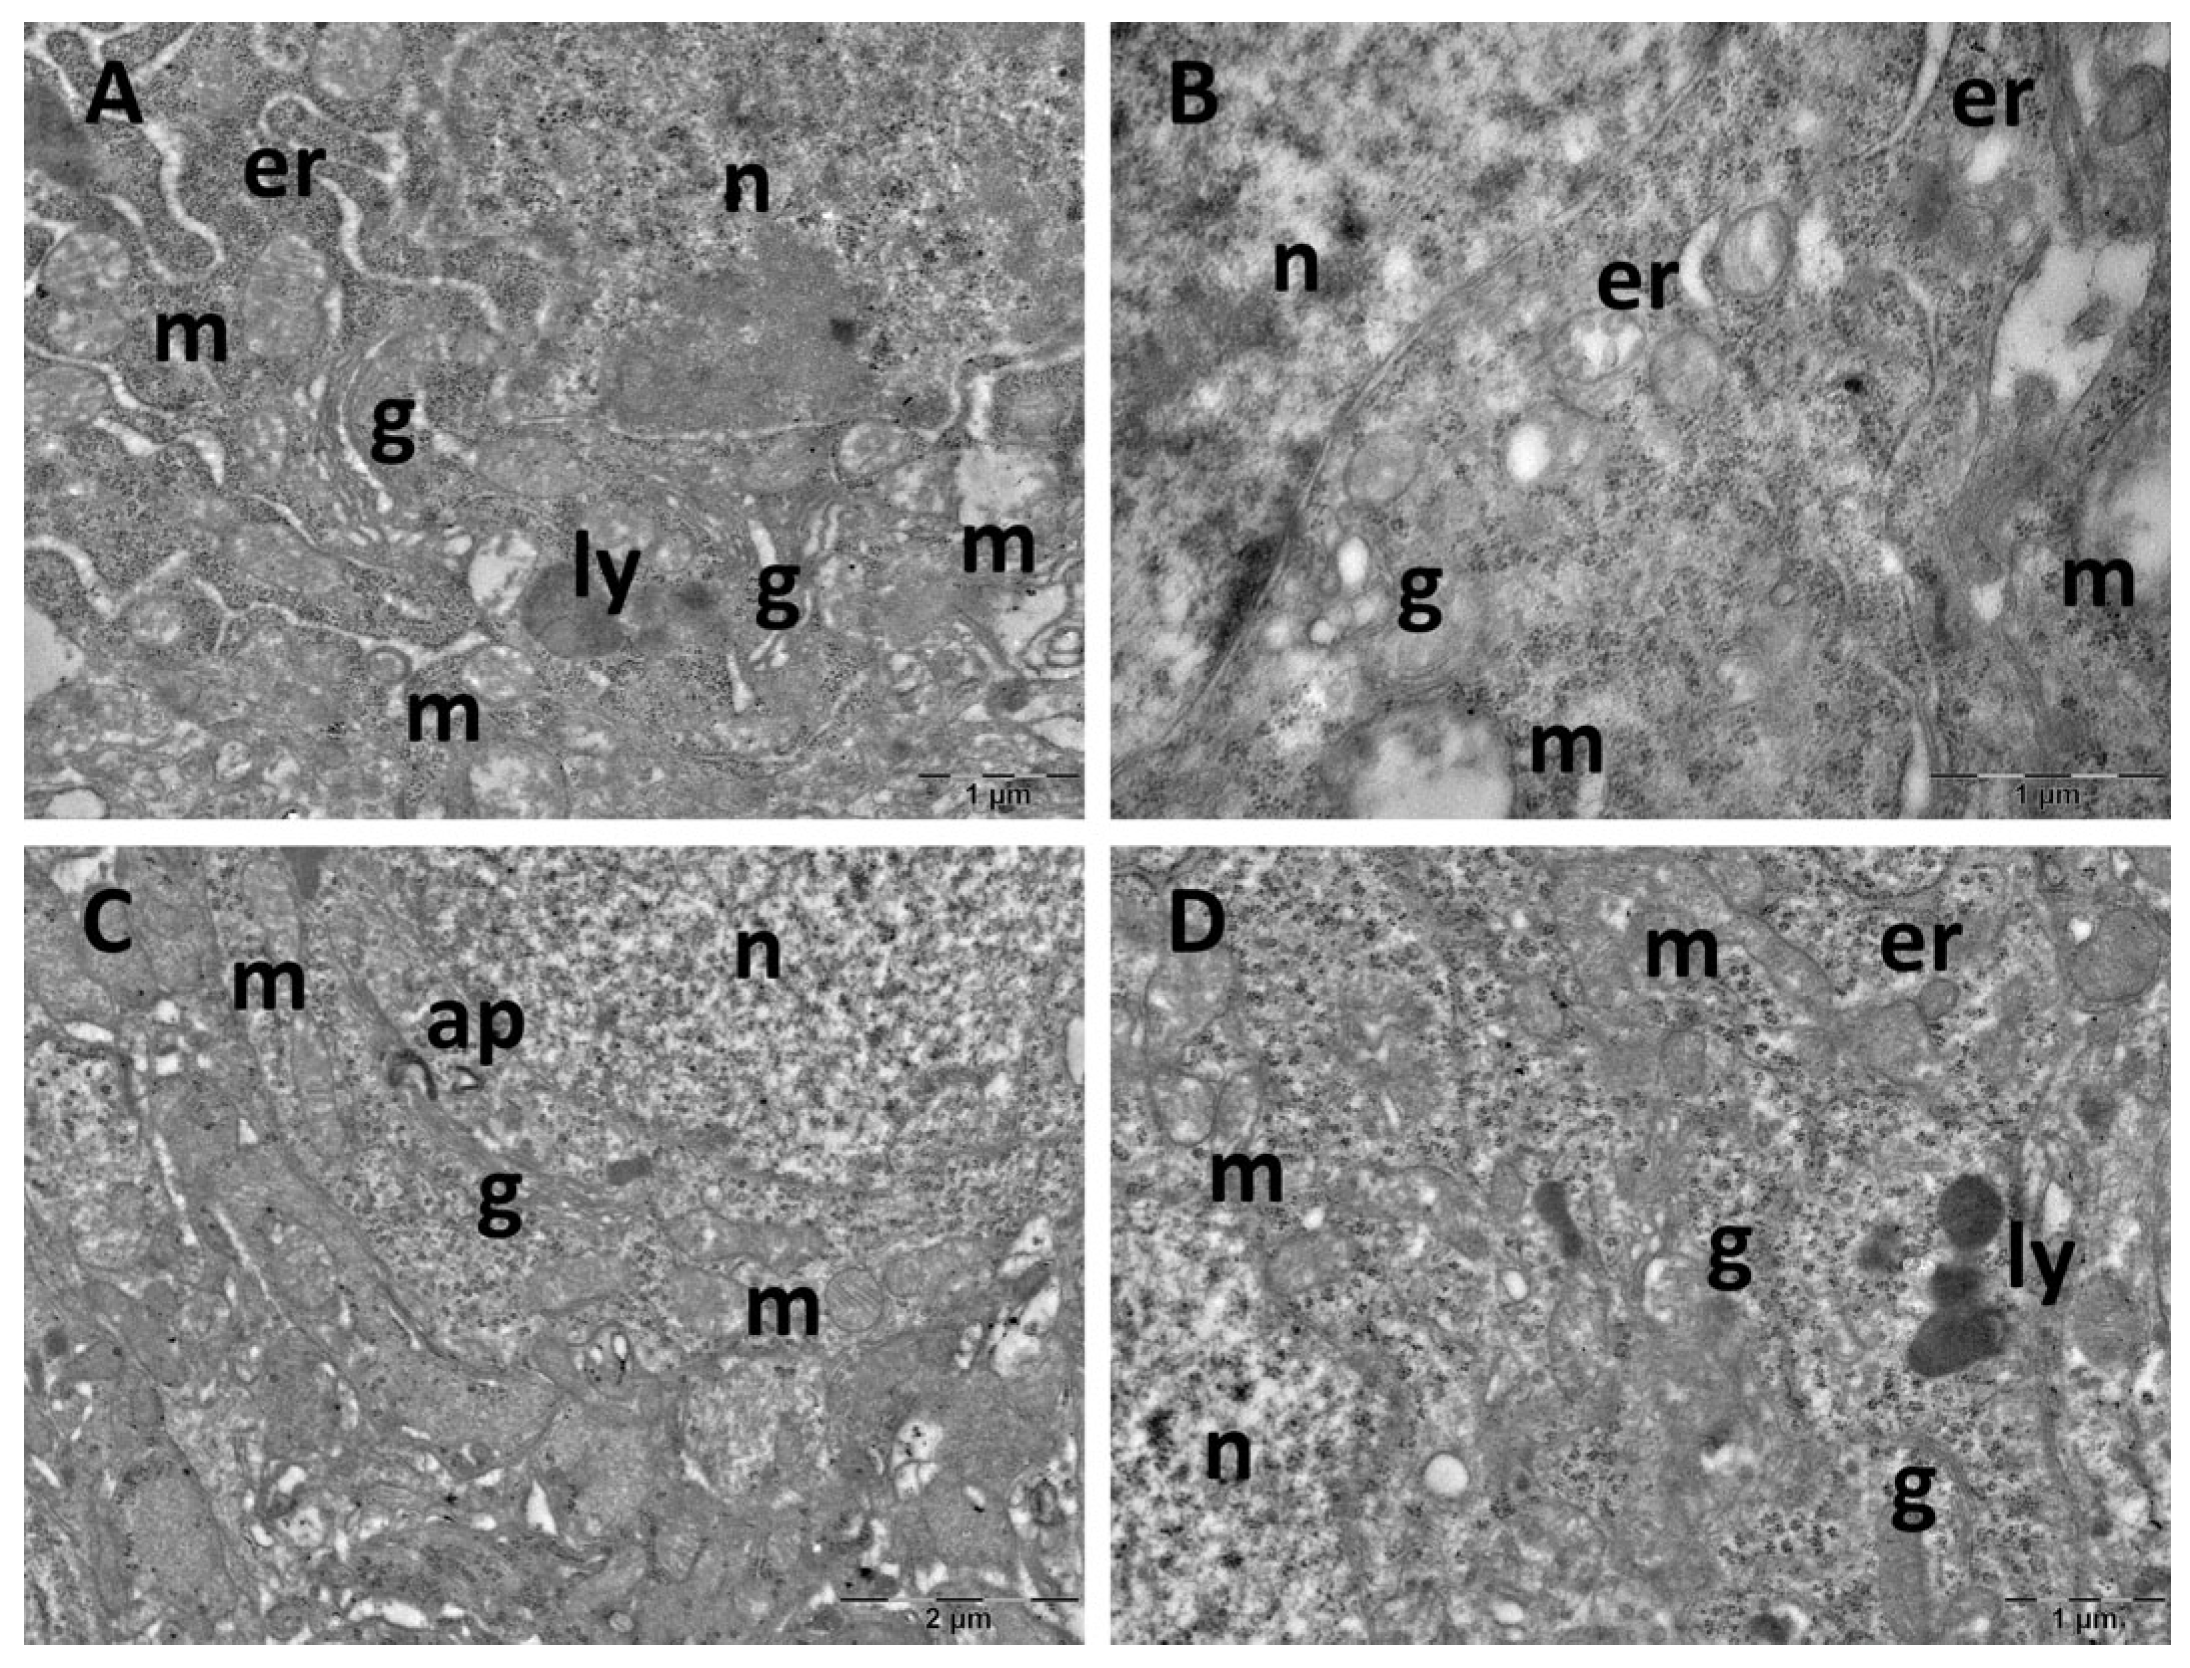

3.4. Brain Transmission Electron Microscopy (TEM) Ultrastructure Changes

- Dai, W.; Xiao, Y.; Tu, Y.; Xiao, F.; Lu, Y.; Qin, Y.; Xie, Y. Propofol Protects Hippocampal Neurons in Sleep-Deprived Rats by Inhibiting Mitophagy and Autophagy. Ann. Transl. Med. 2021, 9, 1427. [Google Scholar] [CrossRef]

- Lu, Y.; Xiao, Y.; Tu, Y.; Dai, W.; Xie, Y. Propofol-Induced Sleep Ameliorates Cognition Impairment in Sleep-Deprived Rats. Sleep Breath. 2023, 27, 181–190. [Google Scholar] [CrossRef] [PubMed]

- Zhang, W.-H.; Yan, Y.-N.; Williams, J.P.; Guo, J.; Ma, B.-F.; An, J.-X. Dexmedetomidine Prevents Spatial Learning and Memory Impairment Induced by Chronic REM Sleep Deprivation in Rats. Sleep Biol. Rhythms 2023, 21, 347–357. [Google Scholar] [CrossRef]

- Wang, L.; Gu, Y.; Zhang, J.; Gong, L. Effects of Sleep Deprivation (SD) on Rats via ERK1/2 Signaling Pathway. Med. Sci. Monit. 2019, 25, 2886–2895. [Google Scholar] [CrossRef] [PubMed]

- Aboufares El Alaoui, A.; Buhl, E.; Galizia, S.; Hodge, J.J.L.; de Vivo, L.; Bellesi, M. Increased Interaction between Endoplasmic Reticulum and Mitochondria Following Sleep Deprivation. BMC Biol. 2023, 21, 1. [Google Scholar] [CrossRef]

- De Vivo, L.; Nelson, A.B.; Bellesi, M.; Noguti, J.; Tononi, G.; Cirelli, C. Loss of Sleep Affects the Ultrastructure of Pyramidal Neurons in the Adolescent Mouse Frontal Cortex. Sleep 2016, 39, 861–874. [Google Scholar] [CrossRef] [PubMed]

- Abushov, B.M. Morphofunctional Analysis of the Effects of Total Sleep Deprivation on the CNS in Rats. Neurosci. Behav. Physiol. 2010, 40, 403–409. [Google Scholar] [CrossRef]